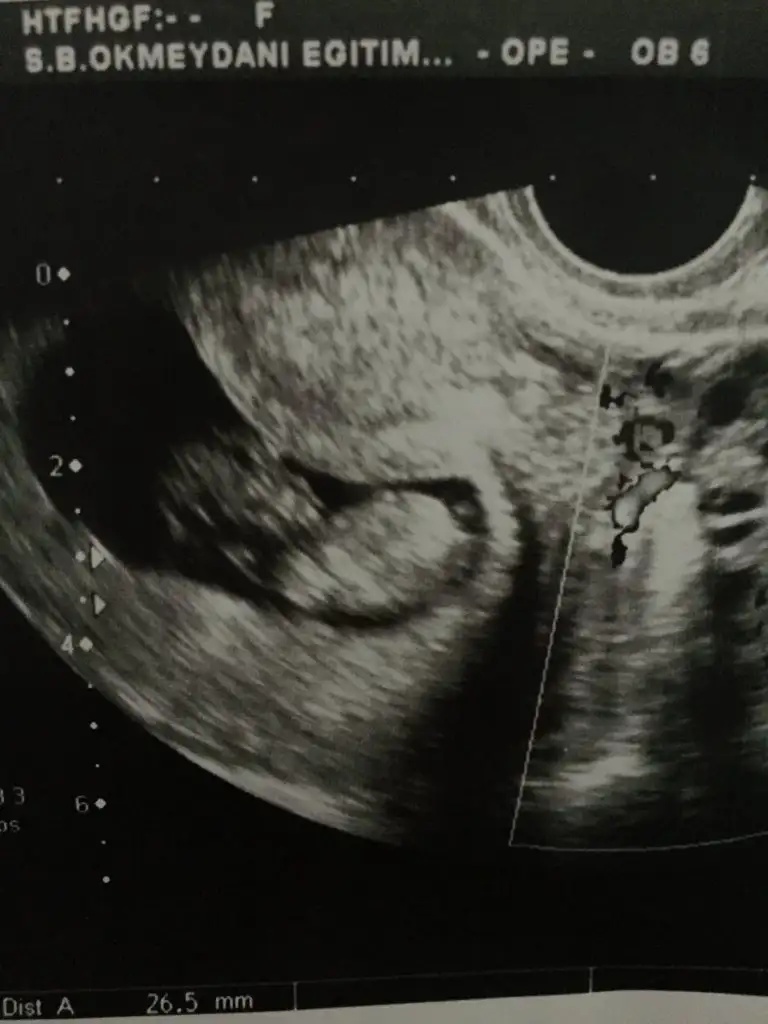

Her iki doktor farkli soyledi cinsiyetini 10ngun sonra kesin soyleriz dedi son fotograflar yeni bacak arasi net dikattli bakinca belki fikrin netlesir belki canimSanki erkek gibi 12 yada 13 hafta usgde paylaşın![]()

Burada kız gibi zaten 12 13 hafta usg istemiştim burada kaç hafta usgHer iki doktor farkli soyledi cinsiyetini 10ngun sonra kesin soyleriz dedi son fotograflar yeni bacak arasi net dikattli bakinca belki fikrin netlesir belki canim![]()

Usg net değil kaç hafta usg 12 13 de paylaşırsınız emin değilim sanki kızKızlar bizede tahminde buluna bilir misiniz vajinal ultrason![]()

11 12 13 hafta usg olmalı burada 14 haftada nub oluşmuş oluyor sanki emin değilim erkek gibi gibi istediğim usg leride paylaşın14 haftalık tahmin edermisiniz

11 hafta 4 gun burda erkekege benzetmistiniz daha once ☺Burada kız gibi zaten 12 13 hafta usg istemiştim burada kaç hafta usg![]()

Evet burada daha önceki usg de nubu erkek gibi bacak arası usg göremedim buradaMerhaba biz 11 hafta olduk tahmin alabilirmiyim☺

Ancak 2 hafta sonra gidebilirim sokaga cikma yasagi olmazsaEvet burada daha önceki usg de nubu erkek gibi bacak arası usg göremedim buradaama 12 13 hafta usg istedim çünki net değildi halada 12 13 hafta usg bekliyorum

10+5 burda Pazartesi kontrolüm var 12+1 olucaz inşallah atarım ozamanUsg net değil kaç hafta usg 12 13 de paylaşırsınız emin değilim sanki kız

Net değil 12 13 haftada paylaşın sanki eminde değilim erkek gibi gibi